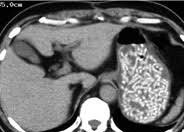

CT検査があるから食事は抜いて来て下さいと言われてるのに、食べて来ちゃう方…時々いますよね… バレてますよ…特に麺類は、麺食べたなこの人ってことまで…笑🫣 (画像は拾いものです)